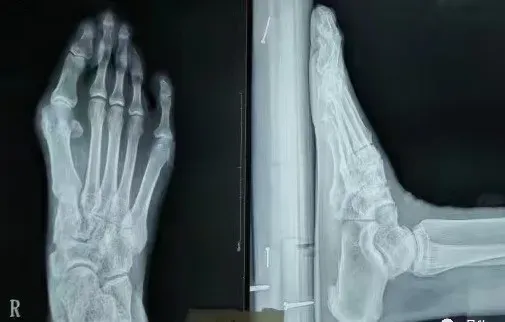

术前术后X光片对比图